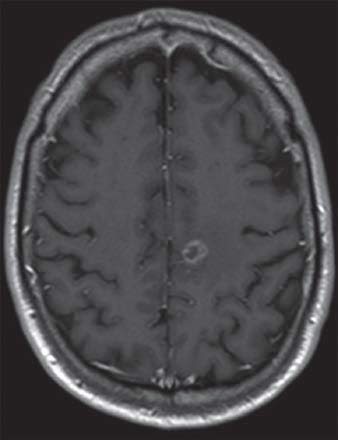

IRM d’un homme de 61 ans présentant des métastases dans l’hémisphère gauche du cerveau secondaire à un cancer du poumon